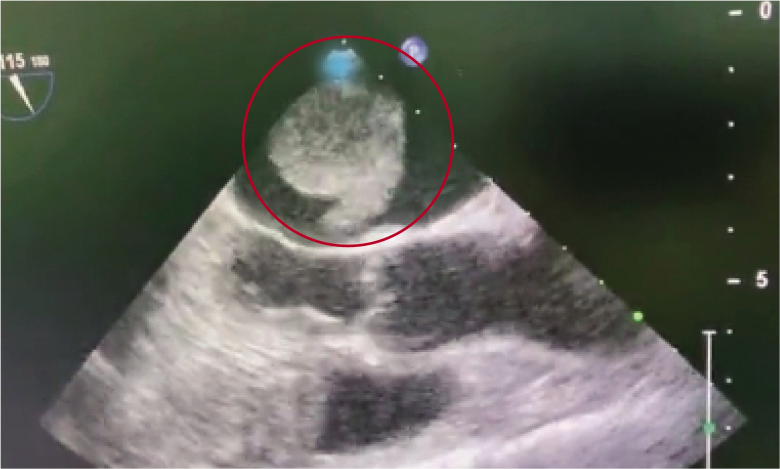

心超检查时,向上“蹦”的肿瘤

王珏介绍,成年人最常见的原发性心脏良性肿瘤之一就是粘液瘤,通常发生在心房,常借助瘤蒂附着于房间隔的卵圆窝边缘,亦可附着于心房游离壁、房室瓣的心房面,粘液瘤会随血流冲击进行有规律的往返运动(扫码可看粘液瘤“蹦跳”的样子,引发医生惊呼)。如果不及时做手术,粘液瘤将扩展到整个心腔,并阻塞血流,引起中风、肺栓塞甚至心梗等疾病。